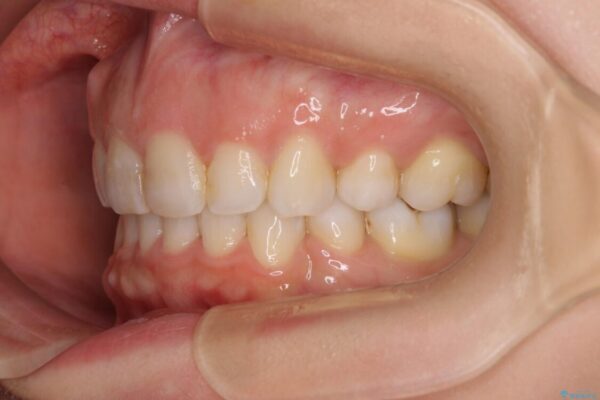

口元の閉じにくさと、奥歯の咬み合わせを気にして来院された患者様です。

治療前

• 【モニター】出っ歯と咬み合わせを改善 ワイヤー装置の抜歯矯正 治療前画像

治療後

• 【モニター】出っ歯と咬み合わせを改善 ワイヤー装置の抜歯矯正 治療後画像